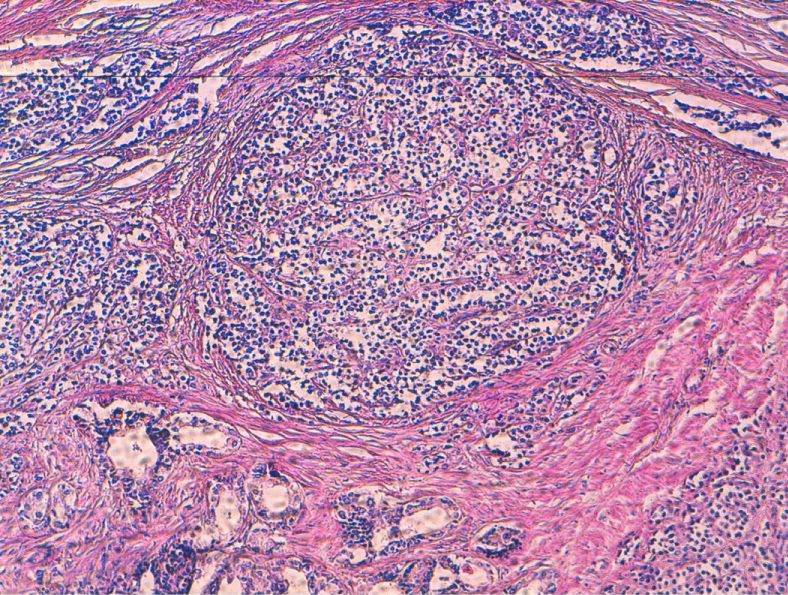

A pelvic Ultrasound revealed a large mass measuring 7 × 5 cm, from lateral right wall of the urinary bladder with no evidence of calculi. Contrast-enhanced computed Tomography Scan confirmed the anatomical location of the mass along with involvement of the adjacent musculature (Figure 1).

Figure 1: Contrast-enhanced CT scan showing mass arising from right wall of the Urinary Bladder (UB). View Figure 1